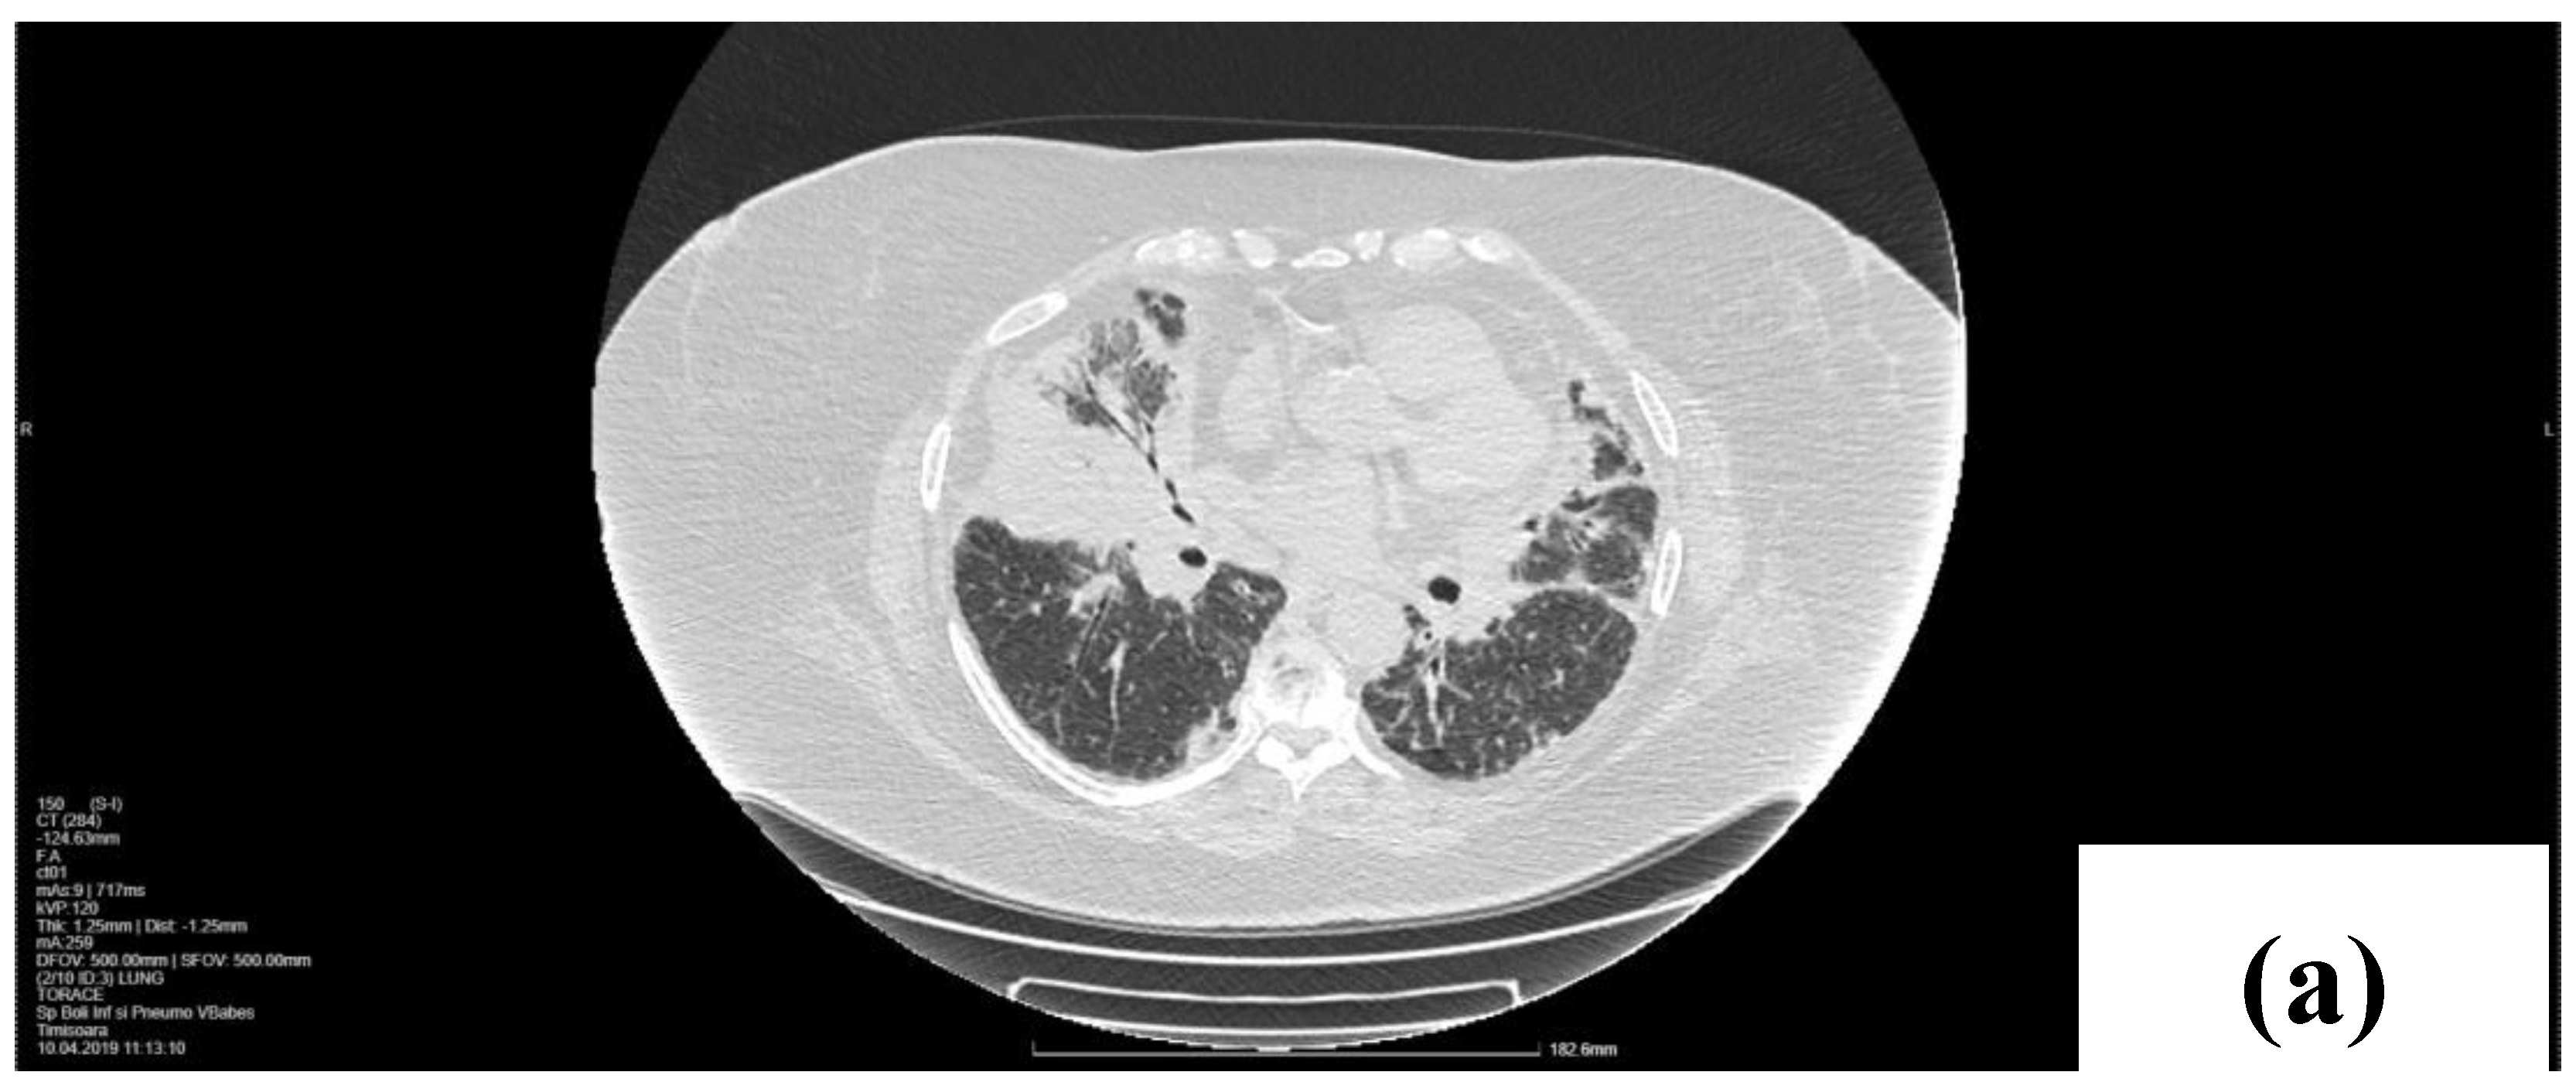

2. Case Presentation

2.1. Laboratory, Radiological, and Histological Examinations